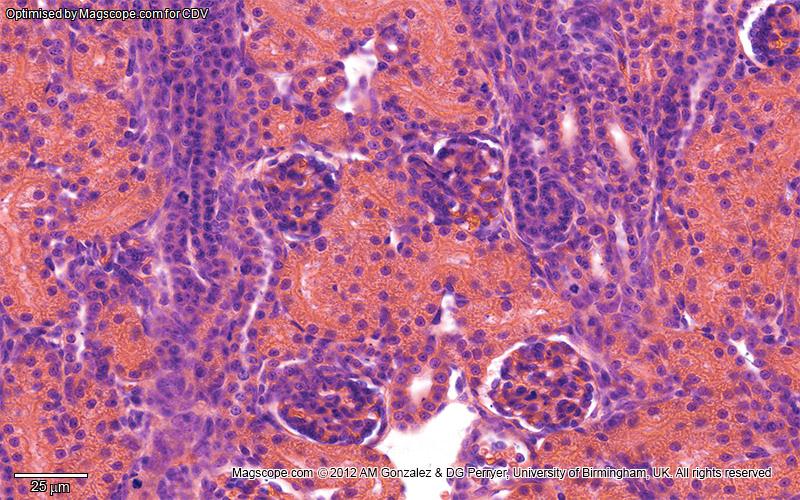

High magnification image of the renal cortex illustrating corpuscles, glomeruli, proximal and distal tubules and collecting tubules

Disability awareness and educational equity: This image has been optimised for red-green colour blind observers who are often unable to differentiate the colours in histological slides, using methods described by Professors Landini and Perryer here.